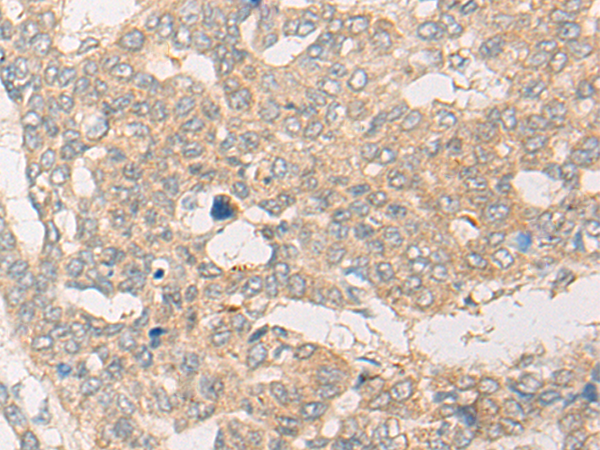

分类: 科研抗体货号: P43575别名: fetal hemoglobin; HBGA; HBGR; HBG-T2; HSGGL1; PRO2979; TNCY; HBG-T1应用: WB,IHC反应种属: Human